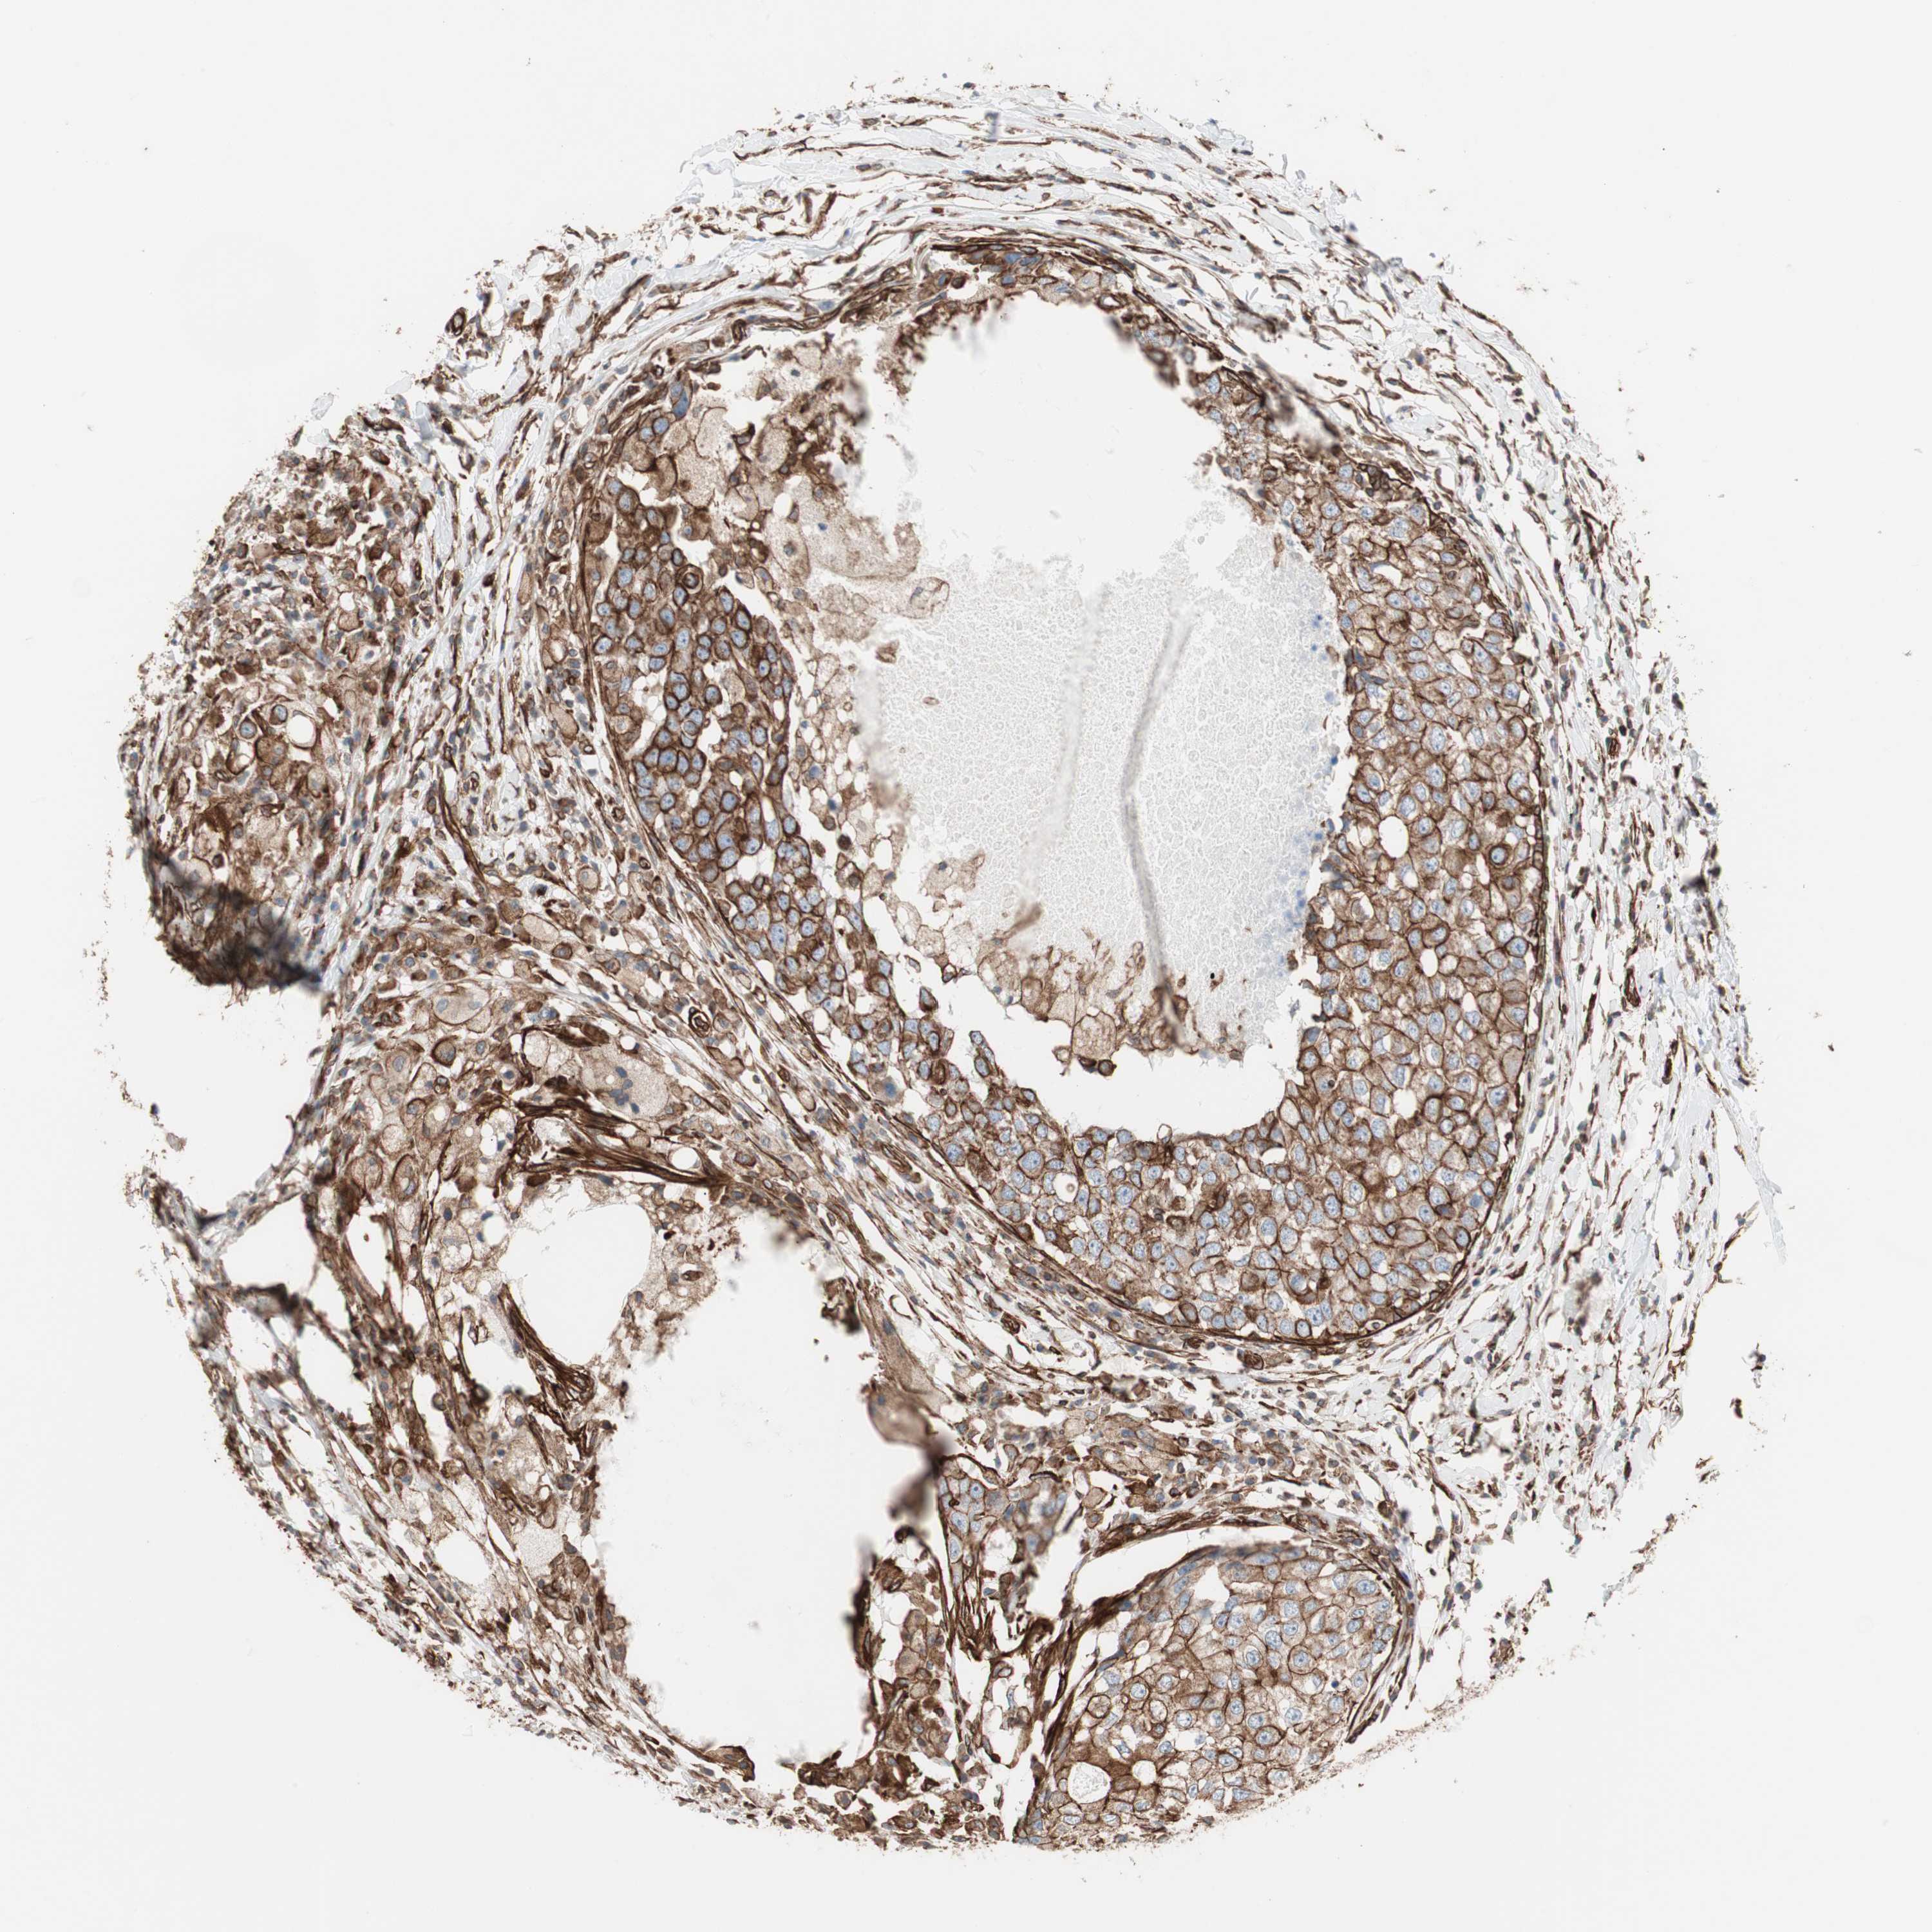

CANCER BREAST CANCER Show tissue menu

BRCA TCGA BRCA VALIDATION PROTEIN EXPRESSION